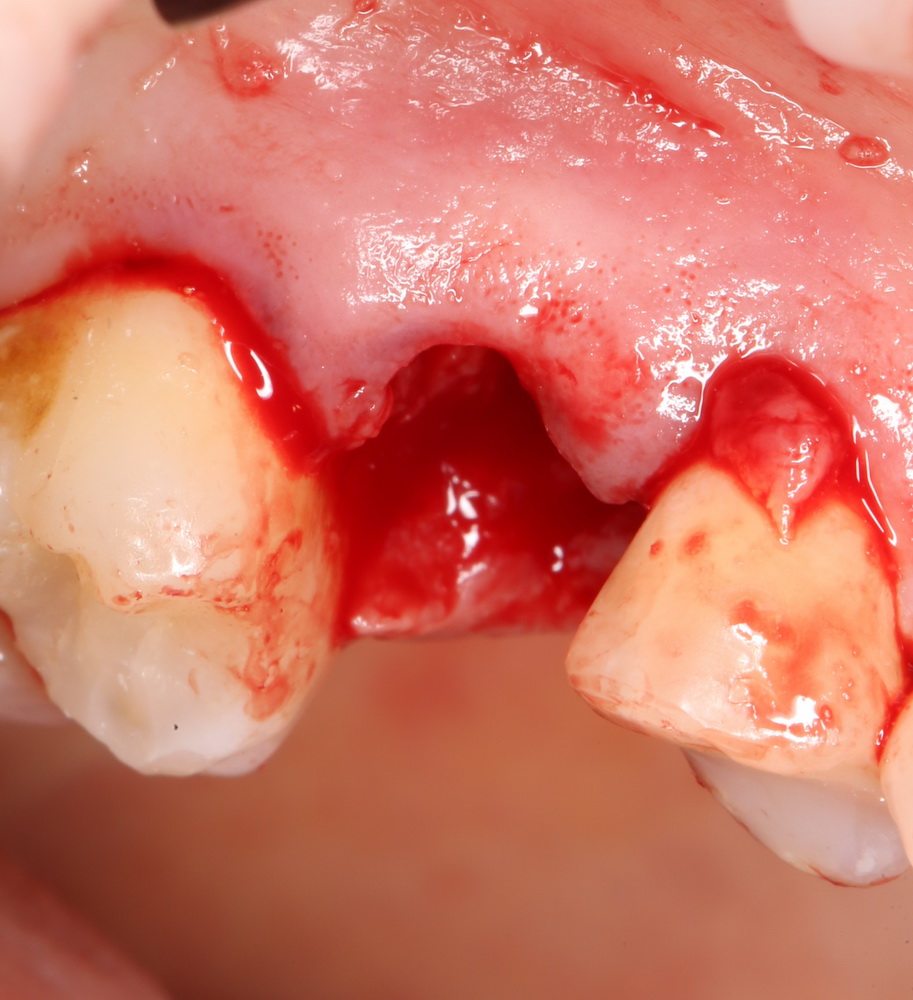

Вот исходная клиническая картинка:

К сожалению, попытка вылечить зуб эндодонтически и восстановить с помощью вкладки/коронки потерпела неудачу. Поэтому приходится его удалять.

Первое, с чего начинается удаление зуба — это разрез. С помощью скальпеля и периотома отделяется круговая связка зуба. Конкретно в этом случае важно еще увидеть границы лунки, чтобы понять пределы аугментации: